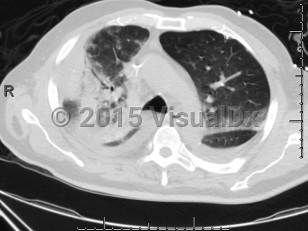

Chlamydophila pneumoniae pneumonia

Chlamydophilia pneumoniae (also known as Chlamydia pneumoniae) is an obligate intracellular bacterium that causes pneumonia.

Transmission of this infection is thought to occur through respiratory droplets, and institutional outbreaks have been reported. Serologic studies have revealed that many adolescents and most adults are seropositive.